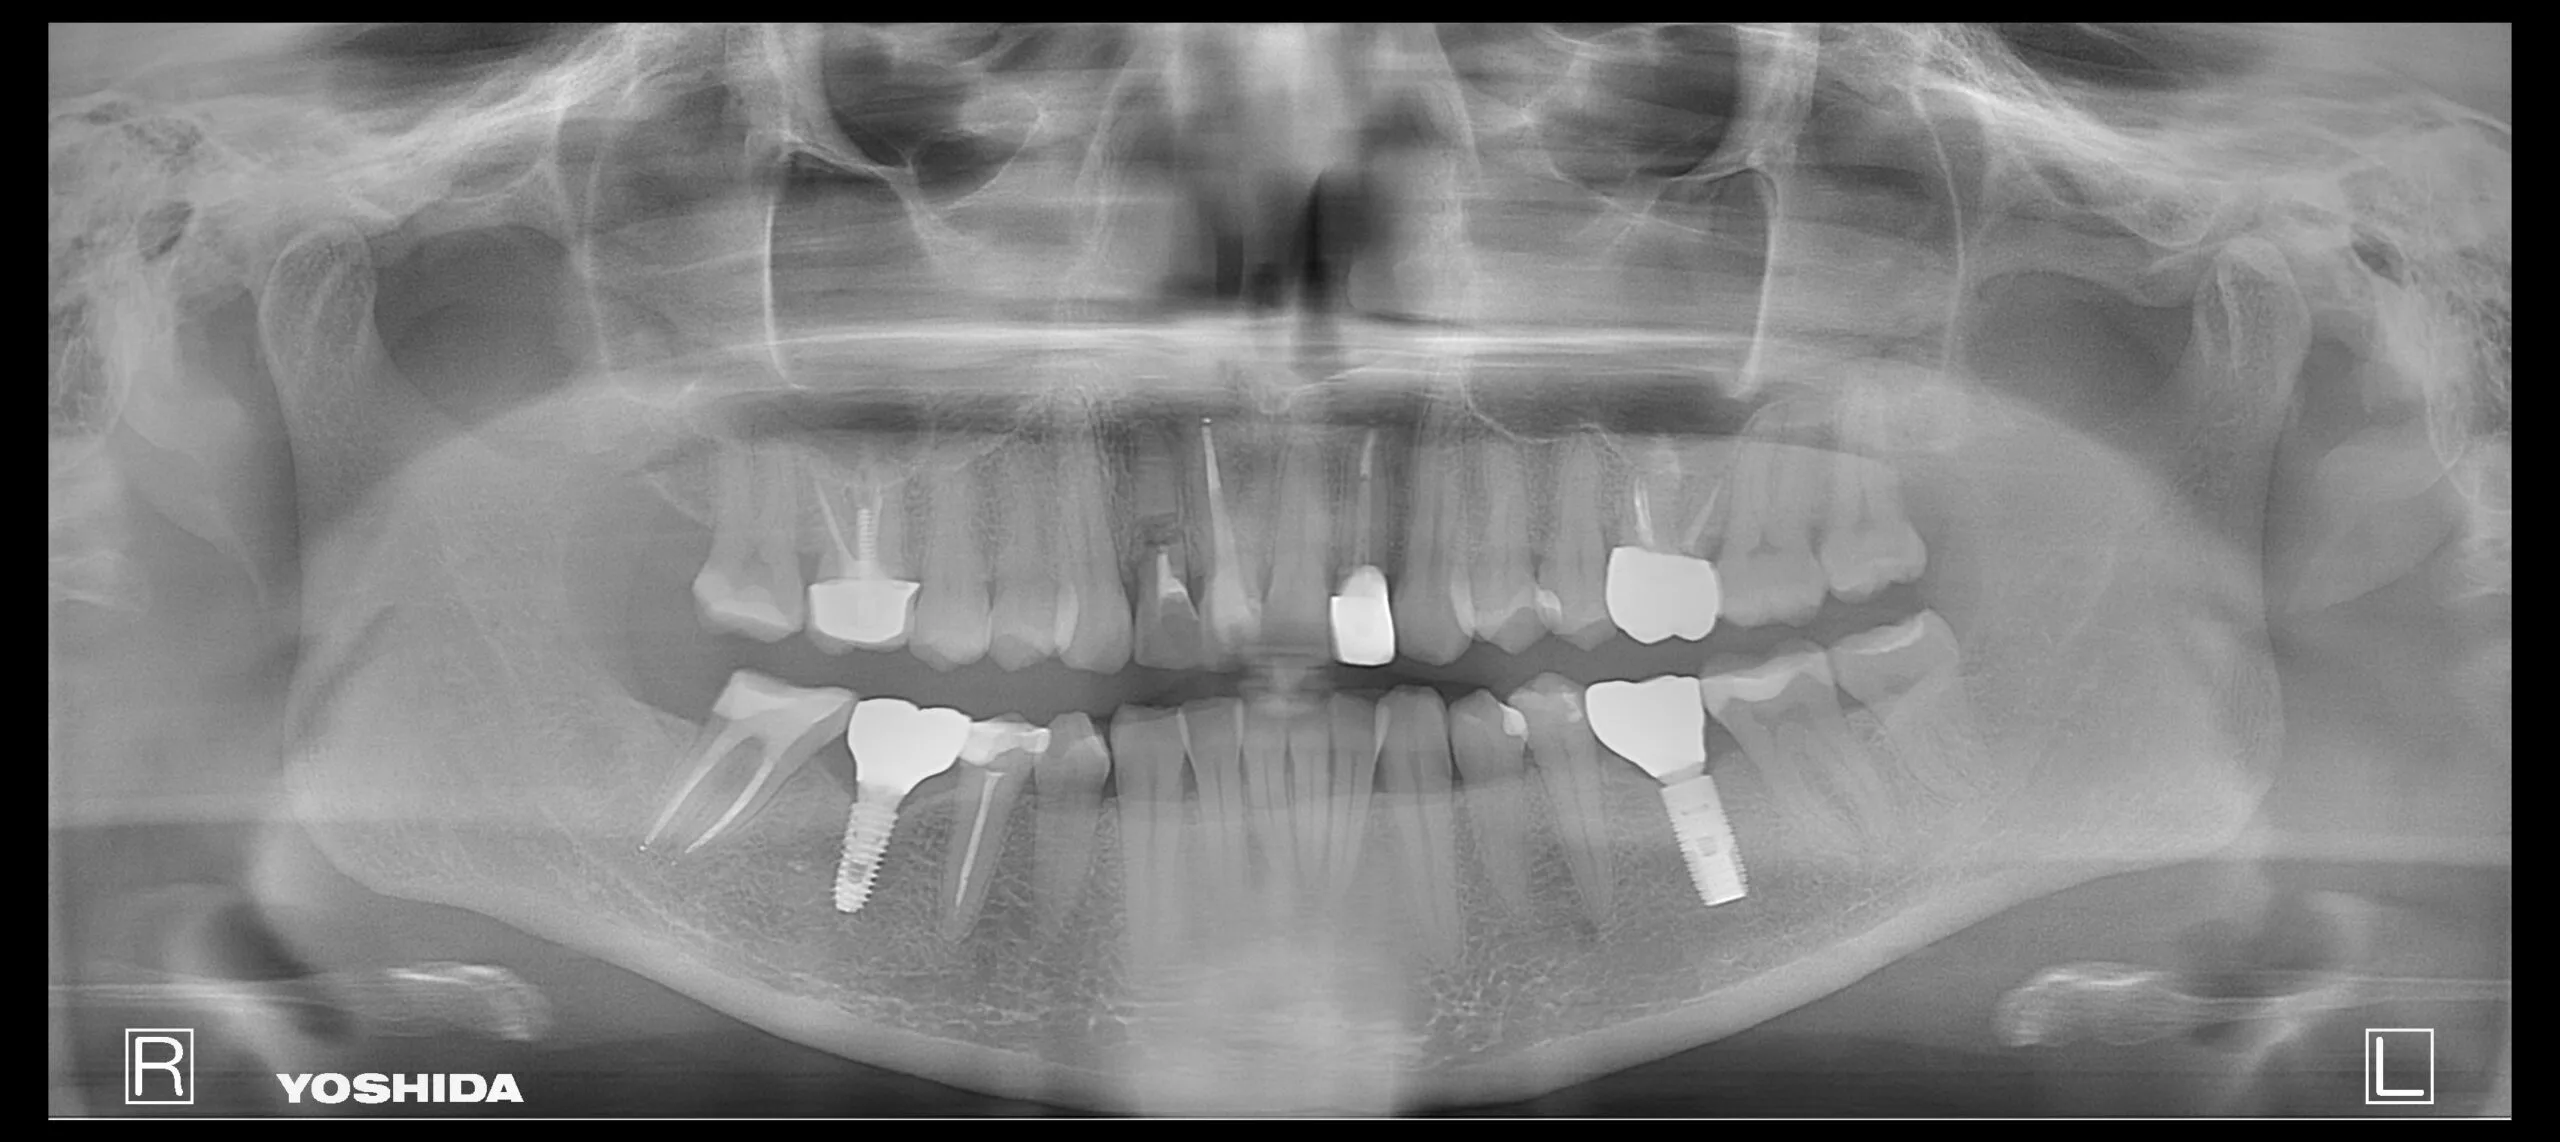

Pacientė kreipėsi dėl skilusių 12 ir 22 dantų šaknų, todėl jautė skausmą ir reikėjo skilusius dantis pašalinti. Pašalinus, buvo įsriegti implantai, jiems prigijus, suformuotos gijimo galvutės ir pritaikyti laikini vainikėliai ant implantų, kad pacientė priprastų prie naujų dantų formos ir pritaikytos spalvos. Net laikinų restauracijų sunku atskirti nuo natūralių dantų ir galime pilnavertiškai džiaugtis savo dantų būkle.